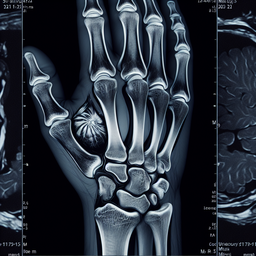

МРТ променезап'ясткового суглобу

Магнітно-резонансна томографія (МРТ) променезап'ясткового суглобу є неінвазивним діагностичним методом, який використовує магнітне поле та радіохвилі для отримання детальних зображень тканин суглобу.